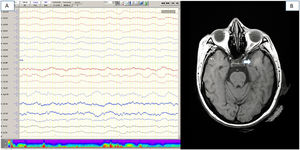

Se realizó RM craneal en 18 pacientes (35,3%), 8 (15,7%) de los cuales estaban alterados. Se observaron alteraciones agudas vasculares en 4 pacientes (7,3%) (2 pacientes con lacunares agudos, un paciente con hemorragia frontal subaguda, un paciente con microsangrados difusos en sustancia blanca). En otros 4 pacientes (7,8%) se observaron hiperintensidades de sustancia blanca, principalmente temporales y mesencefálicas (fig. 1). En estos 4 pacientes la clínica fue confusión leve o moderada en 3 de ellos. No se especifica en cuántos pacientes se realizó secuencia de difusión de la RM.

Pruebas complementarias (paciente número 16). 1A) Electroencefalografía de vigilia, que muestra un enlentecimiento difuso de la actividad bioeléctrica cerebral. 1B) Resonancia magnética craneal (RMN) secuencia FLAIR, que muestra una hiperintensidad focal de sustancia blanca en lóbulo temporal izquierdo.

Se realizó EEG en 16 pacientes (31,3%), mostrando alteraciones sugestivas de encefalopatía difusa leve o moderada en 10 casos (fig. 1), y en 3 de ellos se observaron anomalías epileptiformes sobreañadidas.